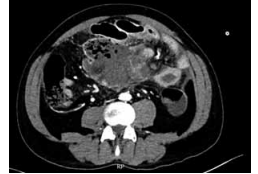

Homem de 53 anos, com quadro de linfoma difuso de

grandes células B com grande conglomerado linfonodal

no mesentério. Iniciou esquema quimioterápico (CHOP)

e, após 1 semana da primeira infusão, apresenta quadro de dor abdominal intensa, procurando o pronto-socorro. Apresenta-se com abdome distendido, doloroso à

palpação de mesogastro, ruídos hidroaéreos ausentes.

FC: 113 bpm e PA: 107 x 74 mmHg. Exames relevantes: hemoglobina: 12 g/dL; hematócrito: 36%; leucócitos:

18.500/mm3

; neutrófilos segmentados: 85%; bastonetes:

10%; plaquetas: 420.000/mm3

; PCR: 220 mg/L. Realizou

ainda a tomografia de abdome demonstrada a seguir:

(Arquivo pessoal; imagem usada com autorização)

Durante a abordagem, no intraoperatório, encontra-se extensa infiltração mesentérica.

Dessa forma, qual conduta deve ser priorizada?